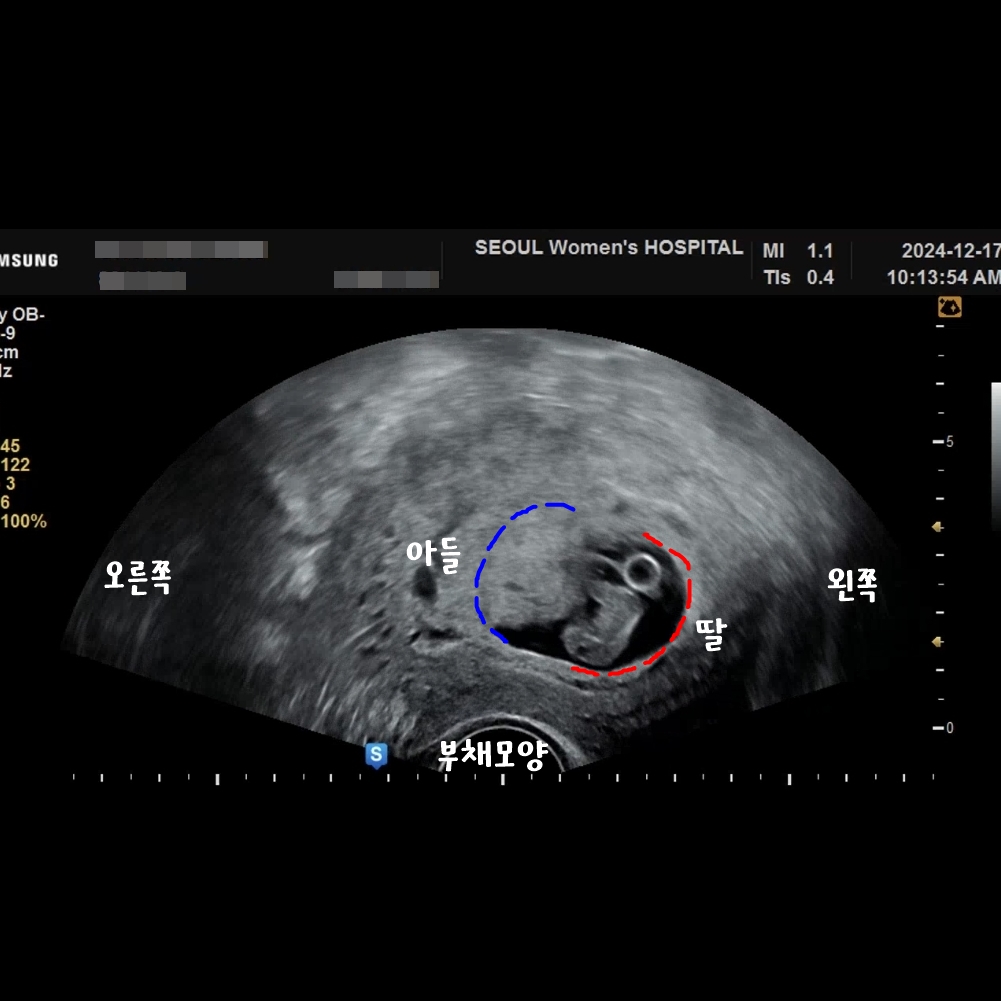

태반위치, 램지법

태반위치인 램지법은 2011년 사이드 램지 박사의 연구에서 나온 이론으로

임신초기(6~8주) 태반의 위치를 통해 태아의 성별을 예측하는 방법이에요.

의학적으로 검증된 예측방법은 아니지만 재미로 확인하심 좋을 거 같아요.

다만 장비에 따라, 질초음파인지 배초음파인지에 따라 좌우가 바뀔 수 있으니 유의해야해요!

램지법 확인방법

1. 질초음파가 전제가 된다.

2. 자신의 초음파 사진이 부채모양인지 아닌지를 확인한다.

3. 태반위치를 확인한다.

태반의 위치가 파란색 : 아들

태반의 위치가 빨간색 : 딸